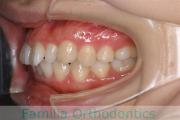

No.22V-296

- 叢生

- 上顎前突

- 19歳

- 女性

- 上:

- 844

- 下:

- 8448

- 主な使用装置:

- FEA

- 治療にかかった費用:

- 88万円

上の出っ歯を治したいとのことで来院されました。下あごの後退が強く、奥歯のすれ違いもありました。上顎のみ左右小臼歯を、親知らずは全て抜歯して、マルチブラケット法を行いました。2年半、30回程度の通院が必要でした。

上野前歯の移動量が大きく、この部位の歯根吸収のリスクが高いケースでした。